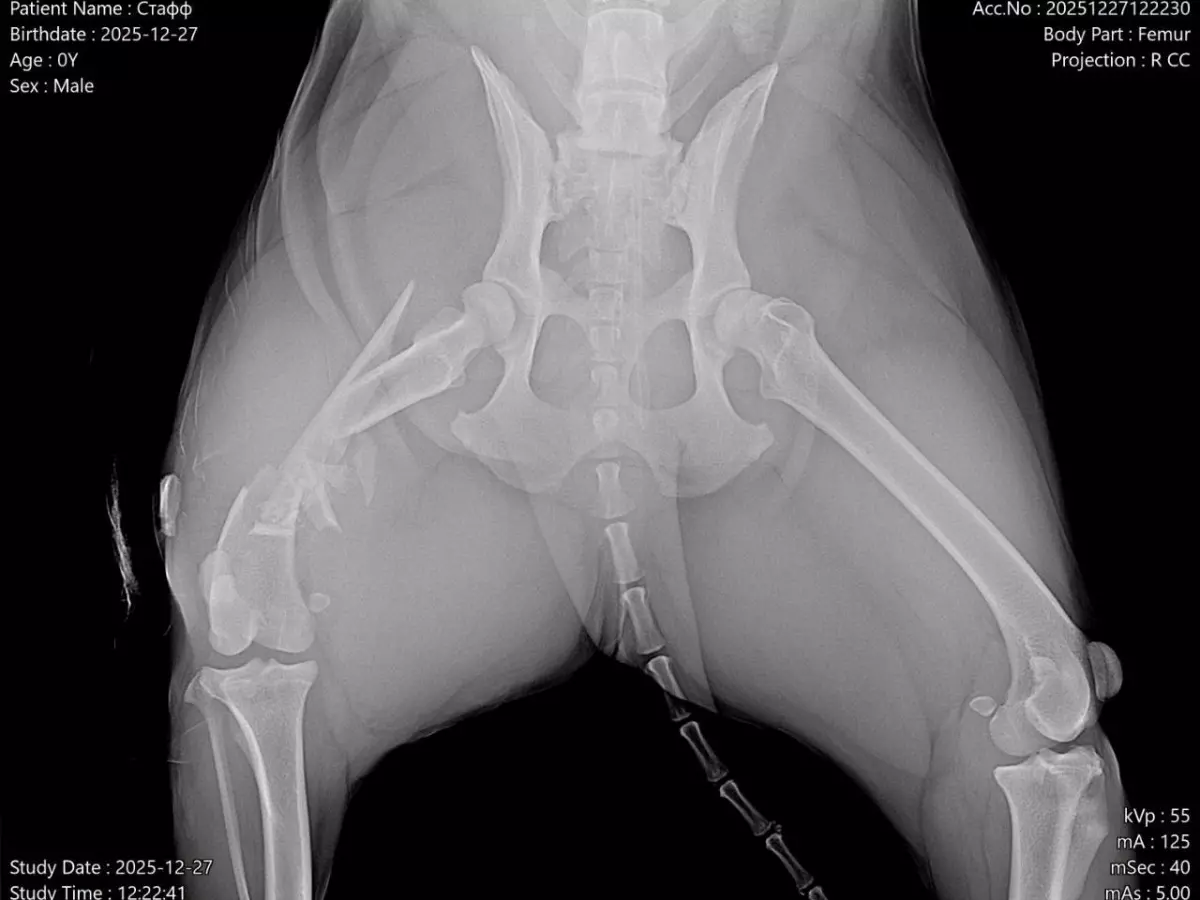

В Азове в переулке Шмидта в конце декабря на обочине нашли пса. По всем признакам домашний питбуль просто замерзал на дороге. Вероятнее всего, беззащитного питомца сбила машина – у пса открытый оскольчатый перелом со смещением.

- Врач собирал кость буквально по кусочкам, - сообщили в приюте. – Все было очень плохо и сложно, но теперь есть шанс на восстановление. Хотя после таких травм функция конечности может не восстановиться никогда.

- Помимо костей, сильно пострадали нервы и мышцы, не исключено, что будет нарушение проприоцепции и неврологический дефицит со снижением болевой чувствительности, но нужны время и длительная реабилитация: содержание в клетке не менее 30 дней, антибиотикотерапия и контроль заживления мягких тканей и костей, - сообщили сотрудникам приюта в ветклинике Ростова.

- Очень хочется, чтобы он полностью восстановился и забыл это все, как страшный сон. Даже чтобы сделать рентген, нам пришлось давать ему наркоз, пёс бился от боли, и с такой травмой он ещё провел все это время, пока его не нашли, на холоде, - сообщают волонтеры.